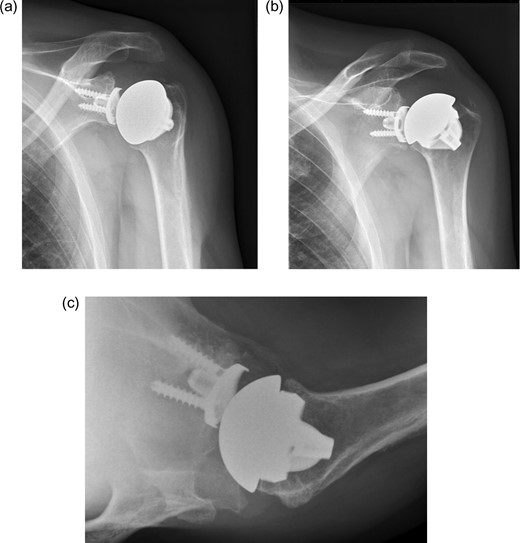

The first case is a 50-year-old man who works as a butcher. He has alkaptonuria, which was confirmed in a biopsy taken at a knee arthroscopy in 2010. He reports pain in his left shoulder. Physical examination shows an active and passively restricted range of motion. Radiological examination (Figure 1) shows glenohumeral osteoarthritis of the left shoulder. MRI shows an intact rotator cuff with signs of tendinopathy. A stemless cementless total shoulder arthroplasty was implanted (Shoulder Modular Replacement (SMR) Stemless, LIMA) (Figure 2). During surgery, the rotator cuff was intact. One year after implantation patient was satisfied regarding pain and functioning, radiography did not show any signs of loosening or other complications.

X-ray of left shoulder of patient with ochronosis. AP external rotation view showing glenohumeral osteoarthritis.

X-ray of left shoulder with total shoulder arthroplasty one year post-operative. (a) AP external rotation view. (b) AP internal rotation view. (c) Axial view.